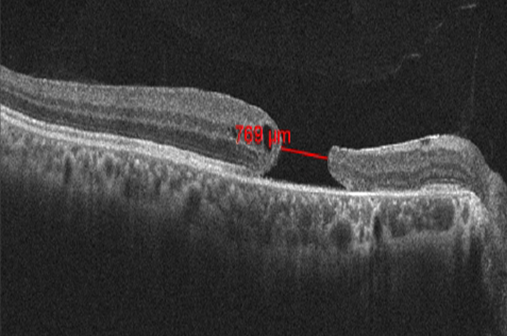

On examination, his best corrected visual acuity (BCVA) was 6/60 in the right eye and 6/6 in the left eye. Intraocular pressure was normal in both eyes. Anterior segment examination results were within normal limits. Fundus examination of the right eye showed a normal optic disc and a large full thickness TMH with no sign of posterior vitreous detachment. Choroidal rupture scar was seen about 3 disc diameters temporal to the fovea and a pigment clump was seen superotemporal to the disc. OCT measured the minimum MH diameter as 769 µ, the basal diameter 1431 µ and height 272 µ. Intraretinal cystic spaces were present on the temporal side of the MH (Figure 1 [Fig. 1]).

Figure 1: Preoperative optical coherence tomography showing full thickness traumatic macular hole. The minimum linear diameter was 769 µm.